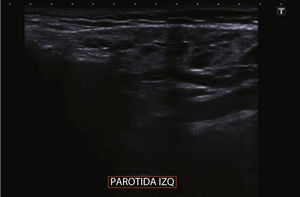

Se trata de una niña de 9 años de edad sana y sin antecedentes personales ni familiares de inmunodeficiencia ni infecciones de repetición. En el último año presenta con frecuencia mensual, episodios de inflamación de ambas parótidas, de 1-2 días de duración, con predominio del dolor durante la masticación, sin asociar fiebre ni otra sintomatología infecciosa. La ecografía cervical es compatible con parotiditis crónica recidivante, ya que muestra múltiples quistes y adenopatías intraparotídeas (figs. 1 y 2).

El diagnóstico de PRJ es fundamentalmente clínico, apoyado en técnicas de imagen. En los últimos años la ecografía5 ha desplazado a la sialografía, ya que muestra una elevada sensibilidad sin necesidad de irradiar al paciente.